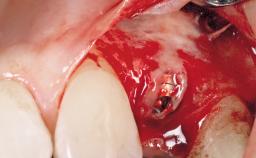

A 29-year-old female patient presented for treatment to replace the upper left central incisor tooth with an implant- supported restoration. The tooth had been intermittently symptomatic for the previous 12 months. The tooth had originally suffered trauma about 15 years previously. Several endodontic treatments had been performed, including an apicectomy procedure to retain the tooth. The patient was healthy and a non-smoker. She had reasonable expectations in regard to esthetic outcomes and the risk of marginal tissue recession following treatment. At medium smile, the gingival margins of the upper teeth were visible, with a display of 3 to 4 mm of the gingival margins. Gingival recession of tooth 21 and a discrepancy in the gingival levels between teeth 11 and 21 was observable during normal speech and smile.

Placement Protocol Immediate implant placement

Tooth Site Maxillary incisor or canine

Socket Morphology Single-root socket

Socket Integrity Damage to one or more bone walls

Bone Volume Damage to one or more socket walls